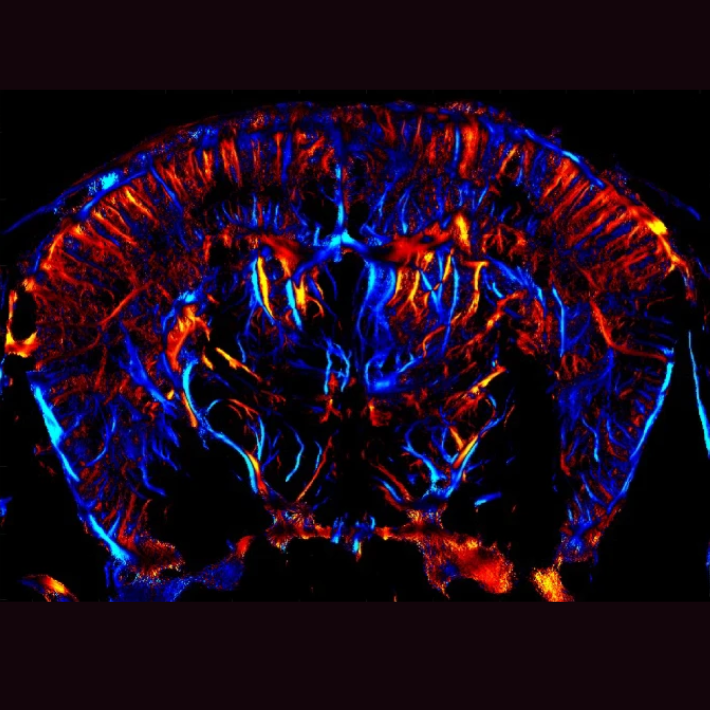

Facioscapulohumerale spierdystrofie (FSHD) is een van de meest voorkomende erfelijke spieraandoeningen. De ziekte is desondanks zeer zeldzaam. In Nederland zijn er ongeveer 2.000 FSHD patiënten en wereldwijd zijn er 500.000 mensen getroffen door de ziekte. FSHD kenmerkt zich door spierzwakte die in de loop van de tijd erger wordt (=progressief). Meestal begint de ziekte in de gezichtsspieren waarna de spieren in de schouders en bovenarm zwakker worden. Welke klachten en hoe snel de ziekte zich ontwikkelt, verschilt van persoon tot persoon. Terwijl sommige patiënten een langzaam ziekteproces doormaken met milde symptomen, krijgen anderen te maken met grotere fysieke beperkingen. Ongeveer 20% van de patiënten verliest uiteindelijk het vermogen om te staan en te lopen en wordt afhankelijk van een rolstoel.

FSHD ontstaat door een verandering in het DNA die leidt tot de ongewenste aanmaak van de transcriptiefactor DUX4 in de spieren van FSHD-patiënten. Transcriptiefactoren spelen een cruciale rol bij het reguleren van genactiviteit. Ze zetten specifieke genen aan (of uit) door te binden aan het DNA. Transcriptiefactoren bepalen niet alleen welke genen aangezet worden maar ook wanneer, waar en in welke mate dit gebeurt. Dit nauwgezette proces vormt de basis voor de juiste ontwikkeling van cellen, organen en het organisme als geheel, waardoor ze gedurende hun leven optimaal kunnen blijven functioneren.

DUX4 is een transcriptiefactor die een belangrijke rol speelt in de eerste stadia van de embryonale ontwikkeling. “Wanneer het embryo uit slechts vier cellen bestaat, zet DUX4 de genen aan die nodig zijn voor de groei en ontwikkeling van een embryo. DUX4 is als het ware een startmotor en geeft het embryonale genoom een kickstart, waarna het snel verdwijnt. Dit snelle verdwijnen is belangrijk omdat DUX4 alleen nodig is tijdens de vroege embryonale ontwikkeling en niet actief hoort te zijn in volwassen weefsels. Bij FSHD-patiënten blijft DUX4 echter ongewenst actief in spiercellen. Dit beschadigt de spieren, veroorzaakt ontstekingen en leidt tot spierzwakte”, zegt professor Silvère van der Maarel.